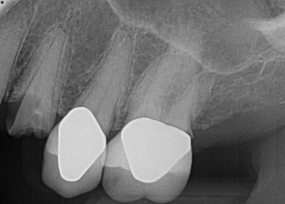

Fig 8. Preoperative periapical radiograph.

Figure 8

Fig 9. 12-week postoperative periapical radiograph.

Figure 9

Essentially, after integration and evaluation of soft tissue at 12 to 16 weeks subsequent to surgical placement of the ceramic implant, the implant is treated similarly to a natural tooth receiving a long-term restoration, and the protocol is the doctor's choice for soft-tissue management at the time of the final impression. Radiographic examination in Figure 8 and Figure 9 revealed that bone volume and soft tissue were preserved, primarily due to exceptional biocompatibility and the PRF biologics implemented after the atraumatic extractions.